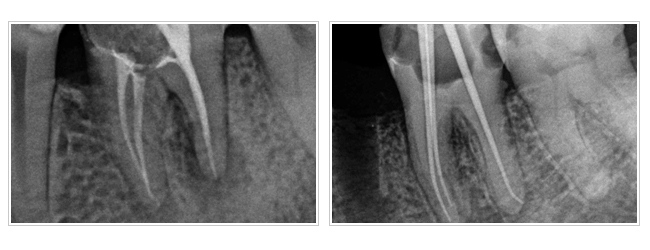

四、複雜根管型態,如:根管分岔、帶狀根管。

根管治療專科醫師,在接受訓練乃至執業後均以能純熟處理上述困難病例為目標,再加上近年來科技的進步,顯微鏡、超音波器械及鎳鈦合金器械被引進根管治療專科的領域,使得根管治療專科醫師得以藉由顯微鏡的強力照明及最大道25 倍的有效放大,看清楚細微根管的深處角落並加以有效清理感染源,保留更多在過去無法保留的牙齒。因此整合了顯微鏡的專科治療,可以稱為顯微根管專科治療。

二、根管治療將受細菌感染的牙神經去除,並將根管清潔擴大。

三、將已經滅菌的根管永久充填,您就可以安心做上假牙。